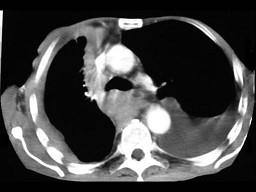

问题 67岁,男,呼吸急促3个月,请结合胸片选出最可能的诊断 ( ) [WXJ-01111.jpg ]

选项 A、肺癌 B、胸膜间皮瘤 C、胸膜肥厚 D、化脓性胸膜炎 E、包裹性胸腔积液

答案 B